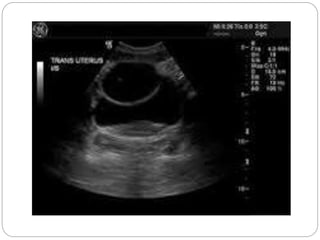

A simple ovariancyst on the right side of the uterus